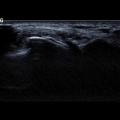

Endométriose profonde

ENDOMETRIOSE

Endometriose ovarienne